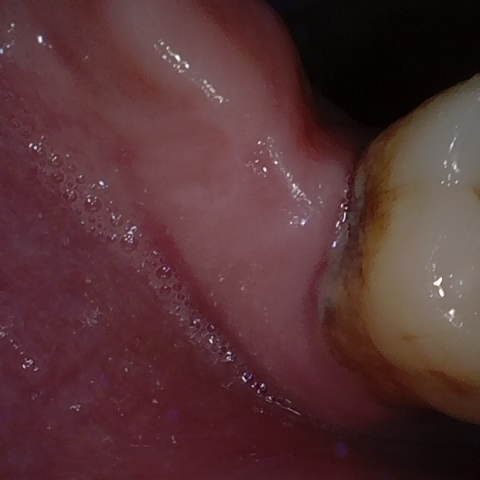

Annotated as "Good"

Original Image Rendering Image